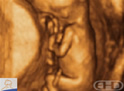

Roteiro: 3 MONATE Zwischen 11 und 12 Wochen erhöht sich das Gewicht des Fötus um fast 60%. Zwölf Wochen markieren das Ende des ersten Drittels oder Trimesters der Schwangerschaft. |

Todas as idades fizeram referência a fecundação, não ao último período menstrual.

Um mês = 4 semanas.